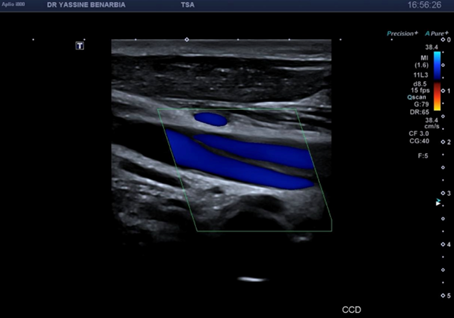

Du côté droit, l'examen met en évidence une dissection du tronc brachiocéphalique (TABC) avec présence d'un faux chenal circulant. Le flap intimal est clairement visible en mode B, séparant le vrai chenal du faux chenal. Au Doppler couleur, on observe un double flux avec des vélocités différenciées : le vrai chenal présente un flux rapide (codé en bleu qui s’éloigne de la sonde) tandis que le faux chenal montre un flux plus lent (codé en rouge qui se rapproche de la sonde).

Les signes retrouvés à l'échographie-Doppler sont : flap intimal mobile visible en mode B séparant vrai et faux chenal, double lumière artérielle en coupe transversale et longitudinale, flux différenciés au Doppler couleur (vélocités élevées dans le vrai chenal, flux plus lent dans le faux chenal), et spectre Doppler pulsé conservé dans le vrai chenal (triphasique ou biphasique).